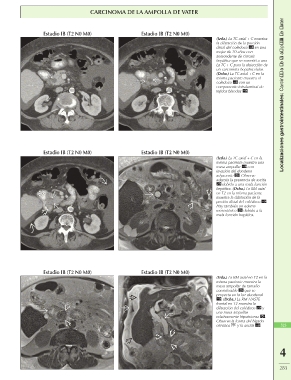

CARCINOMA DE LA AMPOLLA DE VATER

Estadio IB (T2 N0 M0) Estadio IB (T2 N0 M0) (Izda.) La TC axial + C muestra Localizaciones gastrointestinales: Carcinoma de la ampolla de Vater

la dilatación de la porción

distal del colédoco en una

mujer de 70 años con

antecedente de cirrosis

hepática que se sometió a una

La TC + C para la detección de

un carcinoma hepatocelular.

(Dcha.) La TC axial + C en la

misma paciente muestra el

colédoco con un

componente intraluminal de

tejidos blandos .

Estadio IB (T2 N0 M0) Estadio IB (T2 N0 M0)

(Izda.) La TC axial + C en la

misma paciente muestra una

masa ampollar con

invasión del duodeno

adyacente . Observe

además la presencia de ascitis

debido a una mala función

hepática. (Dcha.) La RM axial

en T2 en la misma paciente

muestra la dilatación de la

poción distal del colédoco .

Hay también un edema

mesentérico debido a la

mala función hepática.

Estadio IB (T2 N0 M0) Estadio IB (T2 N0 M0) (Izda.) La RM axial en T2 en la

misma paciente muestra la

masa ampollar de tamaño 523

considerable que se

proyecta en la luz duodenal

. (Dcha.) La RM HASTE

frontal en T2 muestra la

dilatación del colédoco y

una masa ampollar

relativamente hipointensa .

Observe la forma del hígado

cirrótico y la ascitis .